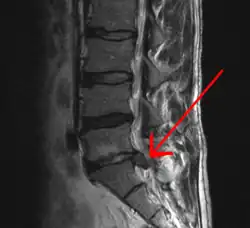

MRI-scan van een lage hernia

- MRI (kernspintomografie). Dit onderzoek is het onderzoek van eerste keus. In vrijwel alle gevallen zal het mogelijk zijn om hiermee de diagnose hernia te stellen.